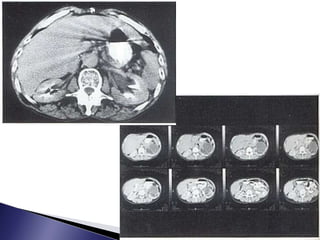

 Alternativa aUIV en pacientes con IRC  Se visualiza el trayecto afectado dilatado que maneja 10UH y hasta 30UH en pionefrosis  Visualiza litiasis y el tejido periureteral  Discrimina si la obstrucción es intrínseca o extrínseca

• 24.

 Nivel liquidolíquido entre contraste y orina retenida  Sitio de estenosis  Signo del borde: trombosis vena renal  Patrón estriado: pielonefritis, contusión renal  Nefrograma persistente: bilateral hTA, o anomalías de la función tubular  Espacio perirrenal húmedo: ingurgitación linfática, edema u orina extravasada